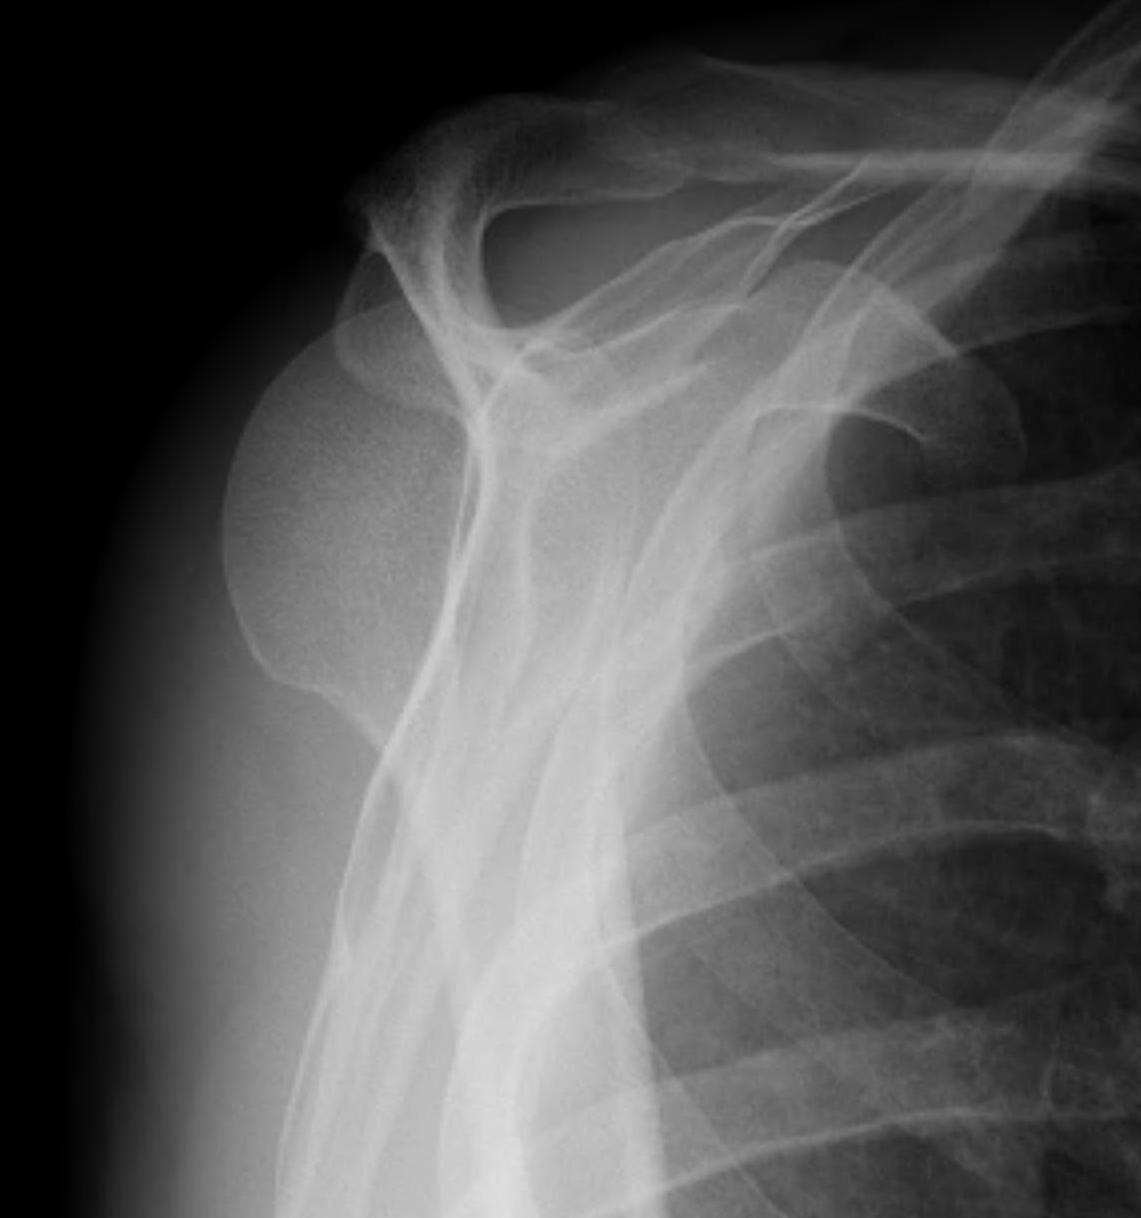

AP Xray

Abnormal overlap of humeral head on glenoid

Light-bulb sign - globular head secondary to internal rotation of the humeral head

Vacant Glenoid Cavity - > 6 mm space between humeral head and anterior rim of glenoid

Posterior shoulder dislocations